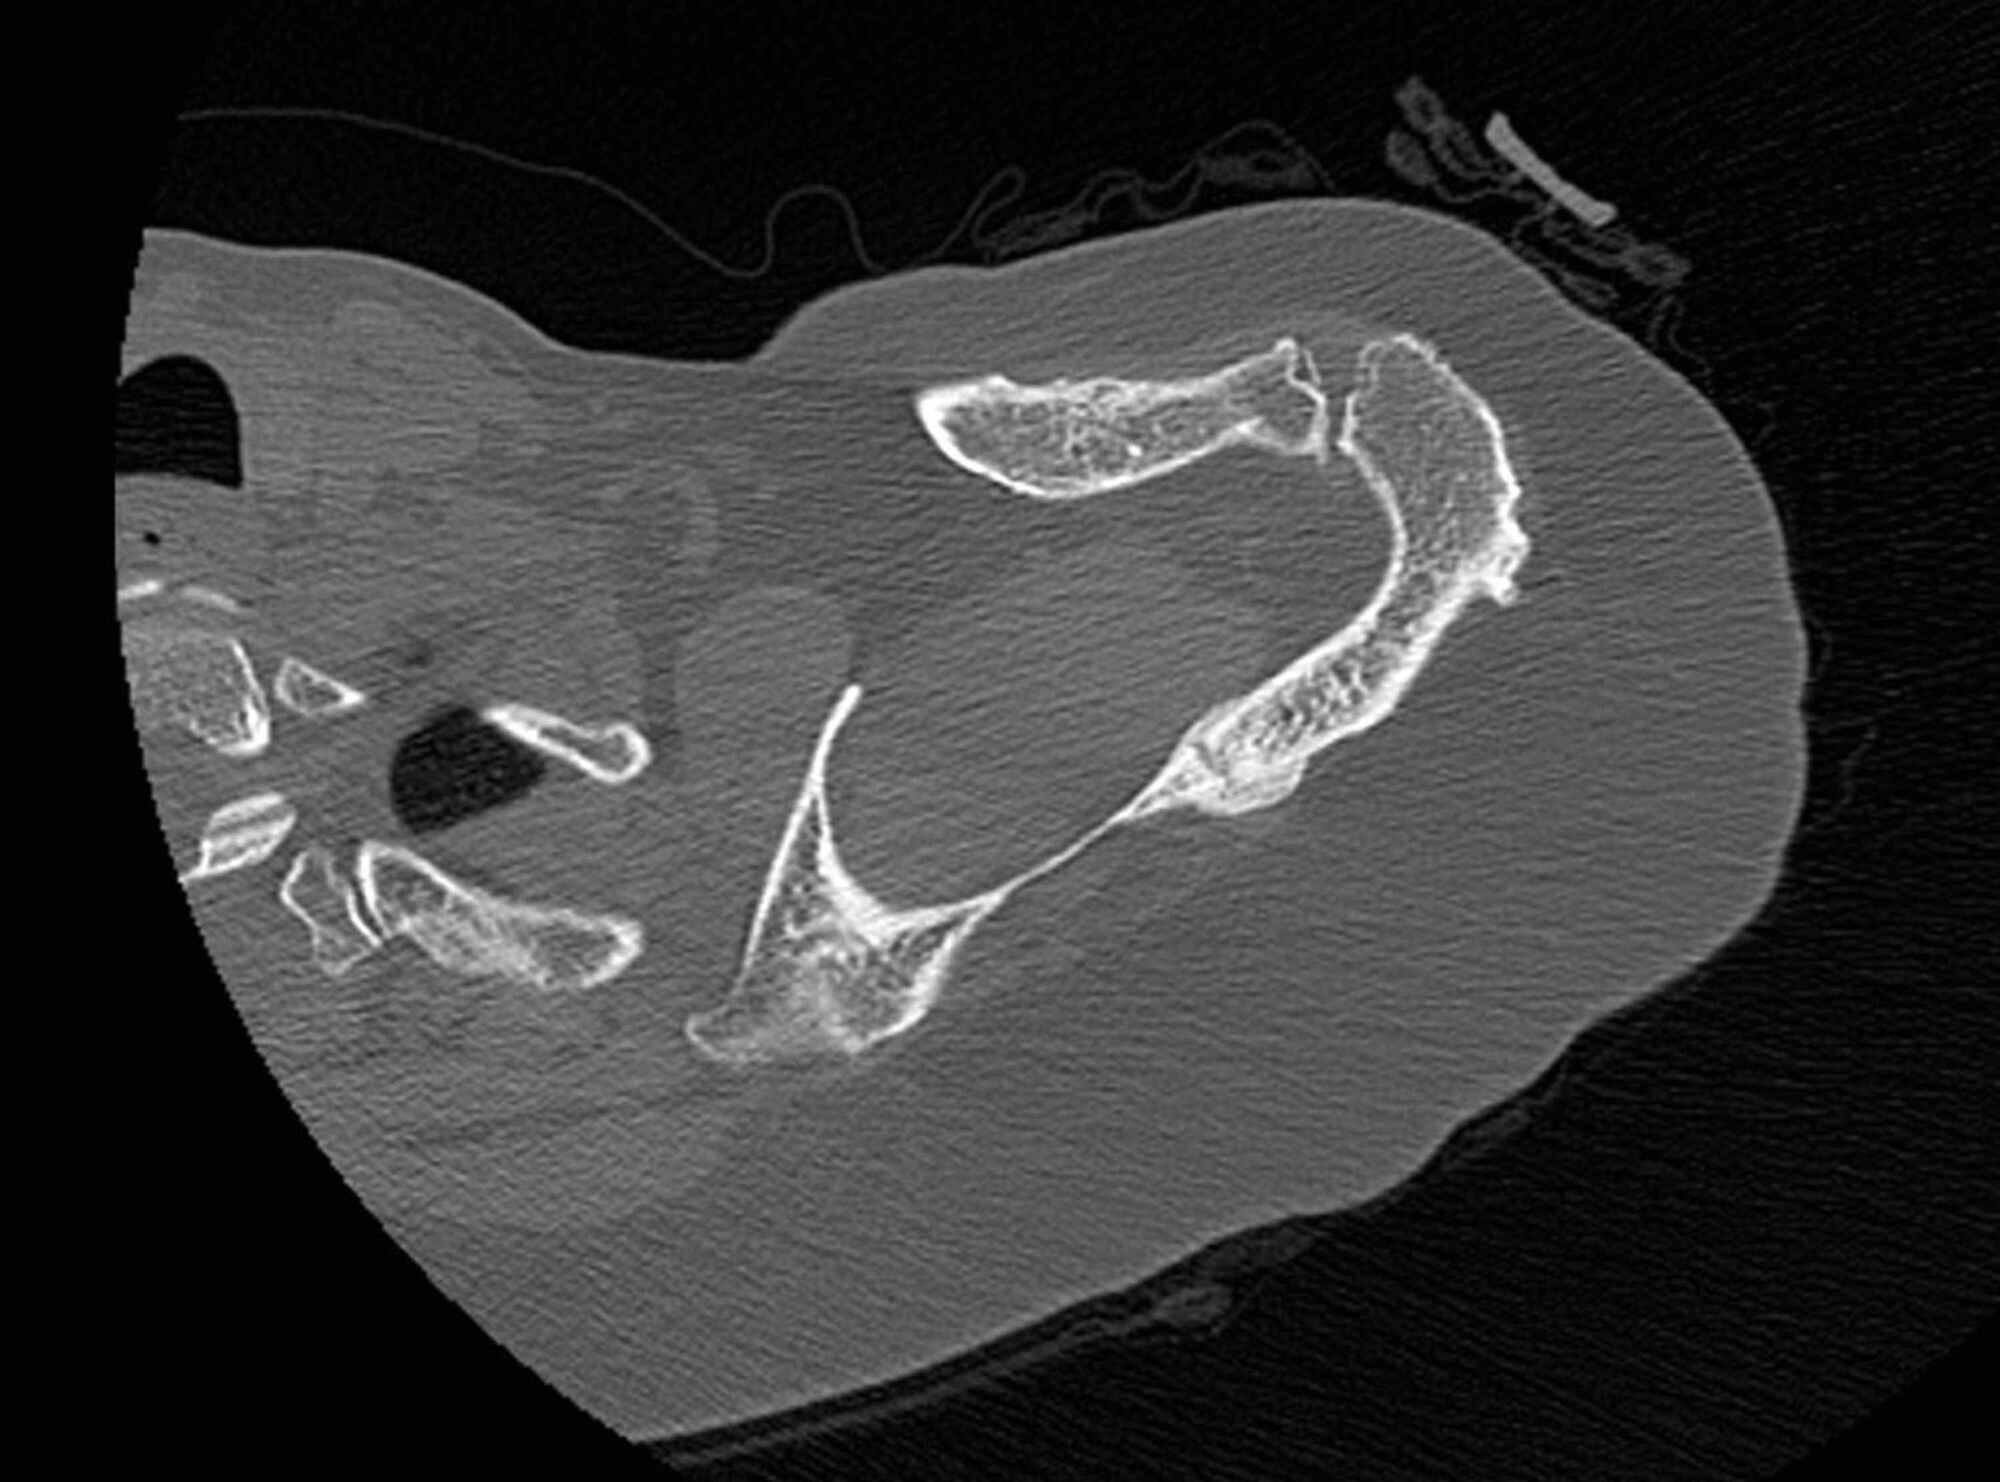

Figure 2 from Scapular stress fracture initially masquerading as tumor Scapula Stress Fracture direct trauma is usually the cause of most scapula fractures. Nonoperative treatments include the use of a sling or shoulder immobilizer, ice and pain medications. scapular spine stress fractures are rare, but can occur in patients with a combination. although some have resulted from trauma and have responded well to. scapula fractures are uncommon injuries, representing. Scapula Stress Fracture.

Scapular stress fracture Image Scapula Stress Fracture scapula fractures are uncommon injuries, representing ~3% of all shoulder fractures. the scapula (shoulder blade) is a bone, shaped somewhat like a triangle, that is protected by a complex system of surrounding muscles. scapula fractures are uncommon fractures to the shoulder girdle caused by high energy trauma and. although some have resulted from trauma and have. Scapula Stress Fracture.